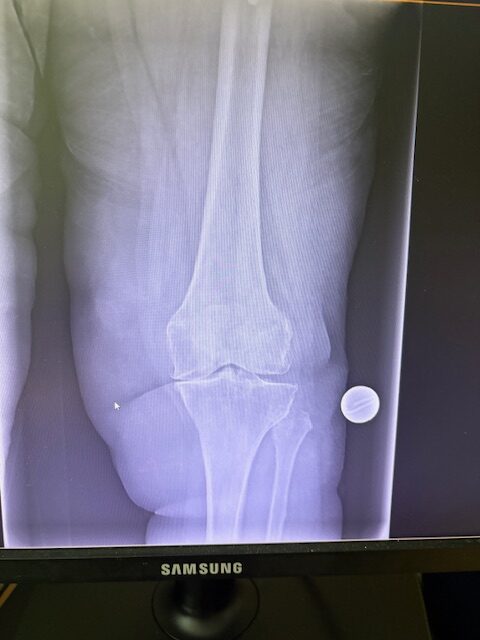

Η 80χρονη ασθενής παρουσίαζε έντονο πόνο και δυσκαμψία στο αριστερό γόνατο τα τελευταία χρόνια. Ο πόνος είχε επιδεινωθεί, επηρεάζοντας τη βάδιση και τη συνολική κινητικότητα, ενώ δυσκολευόταν ακόμα και σε απλές δραστηριότητες όπως το ανέβασμα σκαλοπατιών ή το περπάτημα σε μικρές αποστάσεις. Με την υπάρχουσα πρόθεση ισχίου στην αριστερή πλευρά η ασθενής ήταν αρκετά ευχαριστημένη. Ο ακτινολογικός και κλινικός έλεγχος ανέδειξε προχωρημένη οστεοαρθρίτιδα του αριστερού γόνατος, με πλήρη απώλεια του αρθρικού χόνδρου και παραμόρφωση του μηροκνημιαίου άξονα. Μετά από ανάλυση όλων των επιλογών, αποφασίστηκε η Ολική Αρθροπλαστική Γόνατος με Ρομποτική Υποβοήθηση, με στόχο την απόλυτη ακρίβεια στην τοποθέτηση των εμφυτευμάτων και την αποκατάσταση της φυσιολογικής μηχανικής του γόνατος.

Ο προεγχειρητικός ψηφιακός σχεδιασμός

Πραγματοποιήθηκε σε ειδική ακτινογραφία ολόκληρων των δύο κάτω άκρων. Σε αυτό το ψηφιακό μοντέλο σχεδιάστηκε με ακρίβεια το είδος, το μέγεθος και η ακριβής θέση των προθέσεων, με βάση τα ανατομικά χαρακτηριστικά της ασθενούς.

Τα εμφυτεύματα που χρησιμοποιήθηκαν στο γόνατο της ασθενούς είναι της Aesculap: E-Motion Pro, μηριαίο μέγεθος 4, κνημιαίο μέγεθος 4, με ενθέμα (inlay) 10mm.